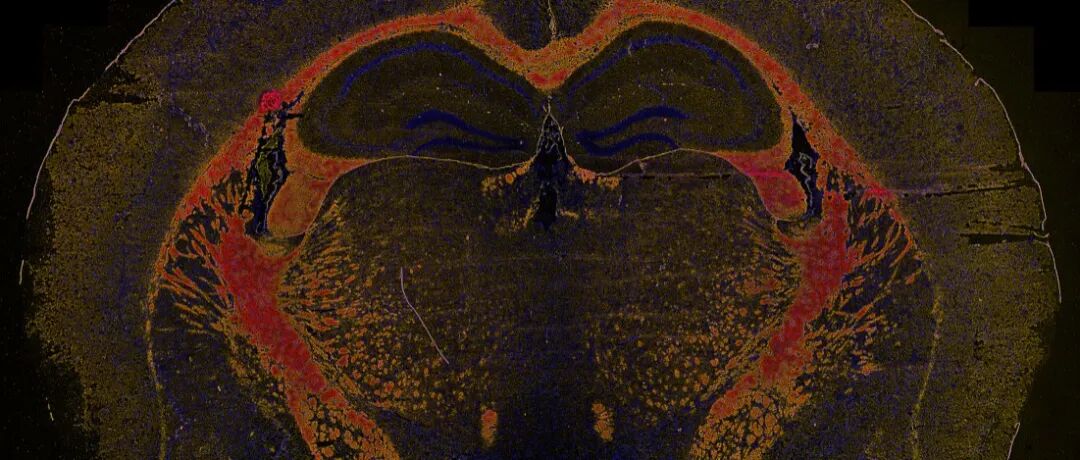

茵菲空间多组学,以IMC为核心的空间多组学

茵菲多组学总结了2025年发表的高水平论文19篇,均采用以成像质谱流式(IMC)为主的多组学技术,如:单细胞测序(scRNA-seq)、单细胞T细胞受体测序(scTCR-seq)、全外显子测序(WES)、全基因组测序(Bulk RNA)、空间转录组、多重免疫组化(mIHC)等。

年终总结:发文合集!